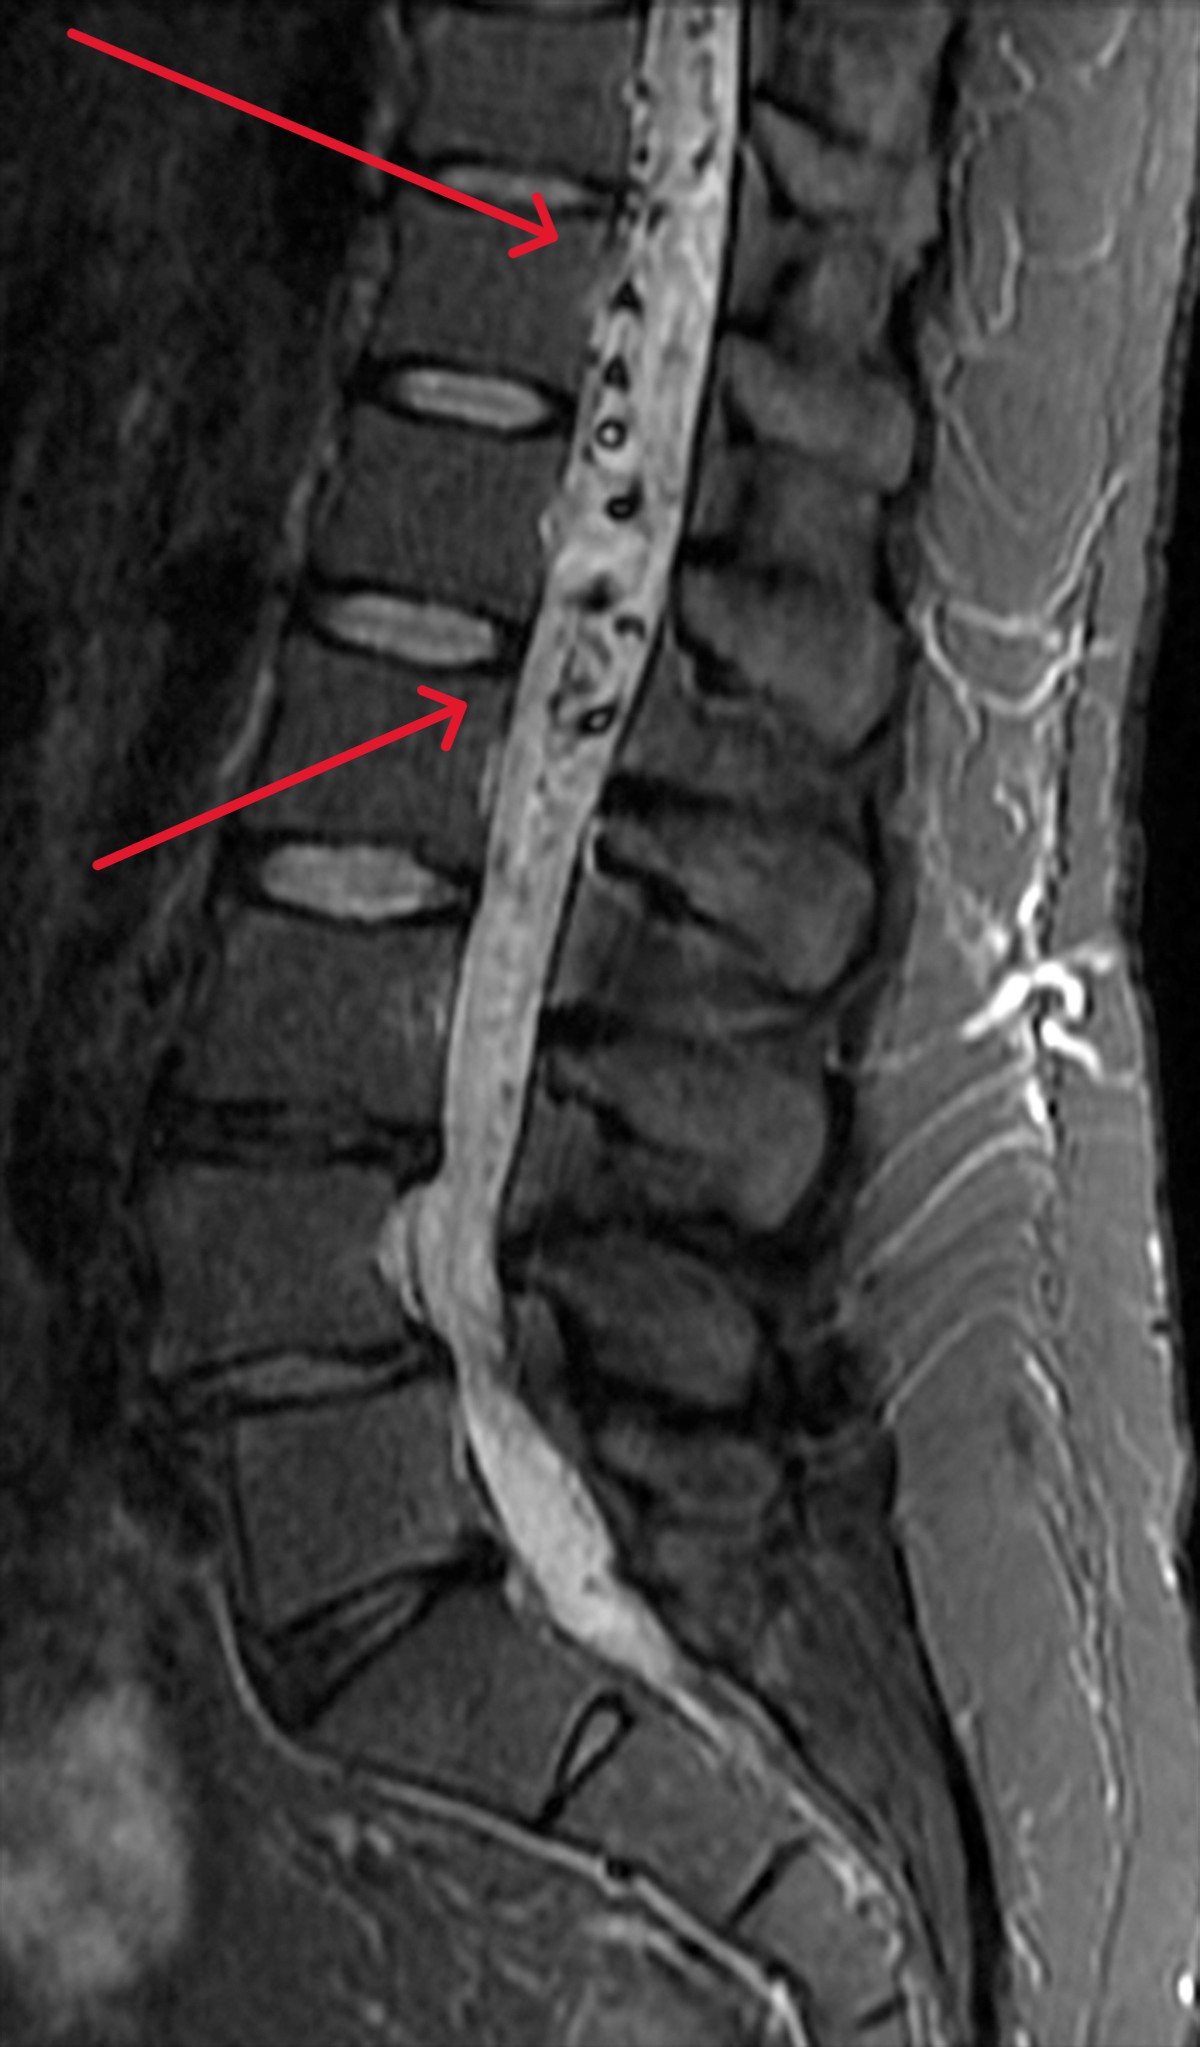

- Magnetic Resonance Imaging (MRI): Imaging studies are crucial in visualizing the spine and spinal cord and identifying any abnormalities. An MRI can reveal areas where blood is moving rapidly, swelling of the spinal cord, or evidence of bleeding.

- Magnetic Resonance Angiography (MRA): This contrast-enhanced MRI scan can provide detailed images of blood vessels to see how blood flows through the body, improving the detection of abnormal vessels. This, in turn, reveals an AVM’s location and size. A contrast dye is sometimes injected to help blood vessels stand out further, though an MRA can also be done without contrast.